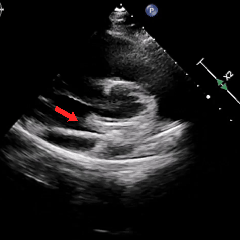

锁定前观察

锁定前多切面观察,确认封堵器左右盘面稳定骑跨于房间隔两侧

成型锁定

前顶钢缆和鞘管,牵拉成型线进行锁定